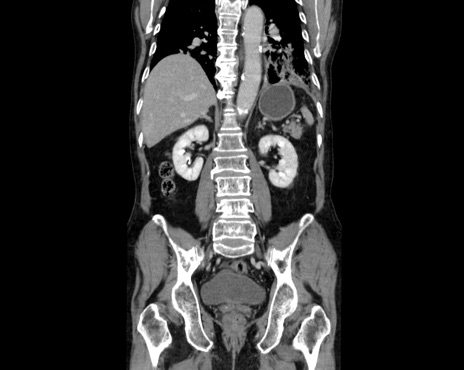

症例26(冠状断像)

【症例】80歳代男性

【主訴】嘔吐

【現病歴】昨晩2回嘔吐あり、今朝になっても嘔吐あり。来院。

【既往歴】胃潰瘍

【身体所見】意識清明、BT 37.6℃、BP 166/95mmHg、HR 100bpm、SpO2 97%、腹部:平坦・軟、腸蠕動音聴取良好、圧痛なし。

【データ】WBC 21900、CRP 1.4